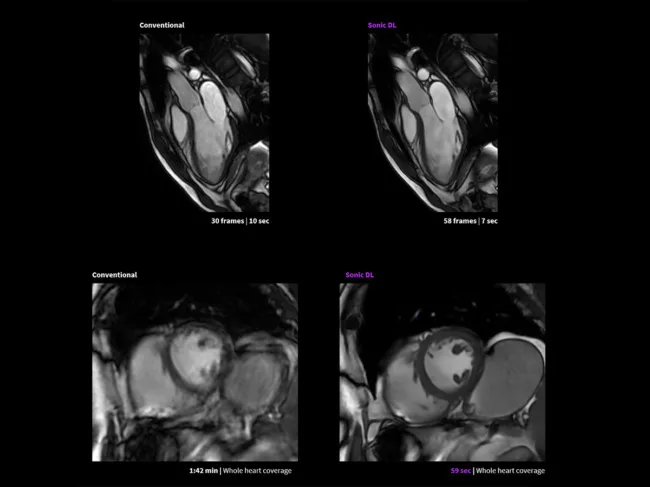

Sonic DL imaging vs. conventional

FDA clears GE’s AI-powered Sonic DL for faster MRI

GE Healthcare Technologies Inc. has launched Sonic DL, a deep learning technology designed to significantly accelerate magnetic resonance imaging (MRI) exams, after receiving regulatory clearance from the U.S. FDA. Read More